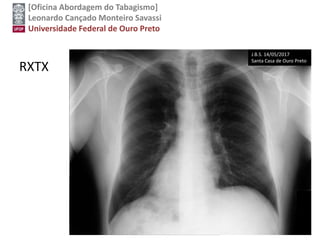

RXTX

J.B.S. 14/05/2017

Santa Casa de Ouro Preto

Citologia de escarro para células cancerígenas

Screening Tests

Low-dose computed tomography has shown high

sensitivity and acceptable specificity for the

detection of lung cancer in high-risk persons.

Chest radiography and sputum cytologic

evaluation have not shown adequate sensitivity or

specificity as screening tests. Therefore, LDCT is

currently the only recommended screening test for

lung cancer.

VOLTARUSPSTF, 2014